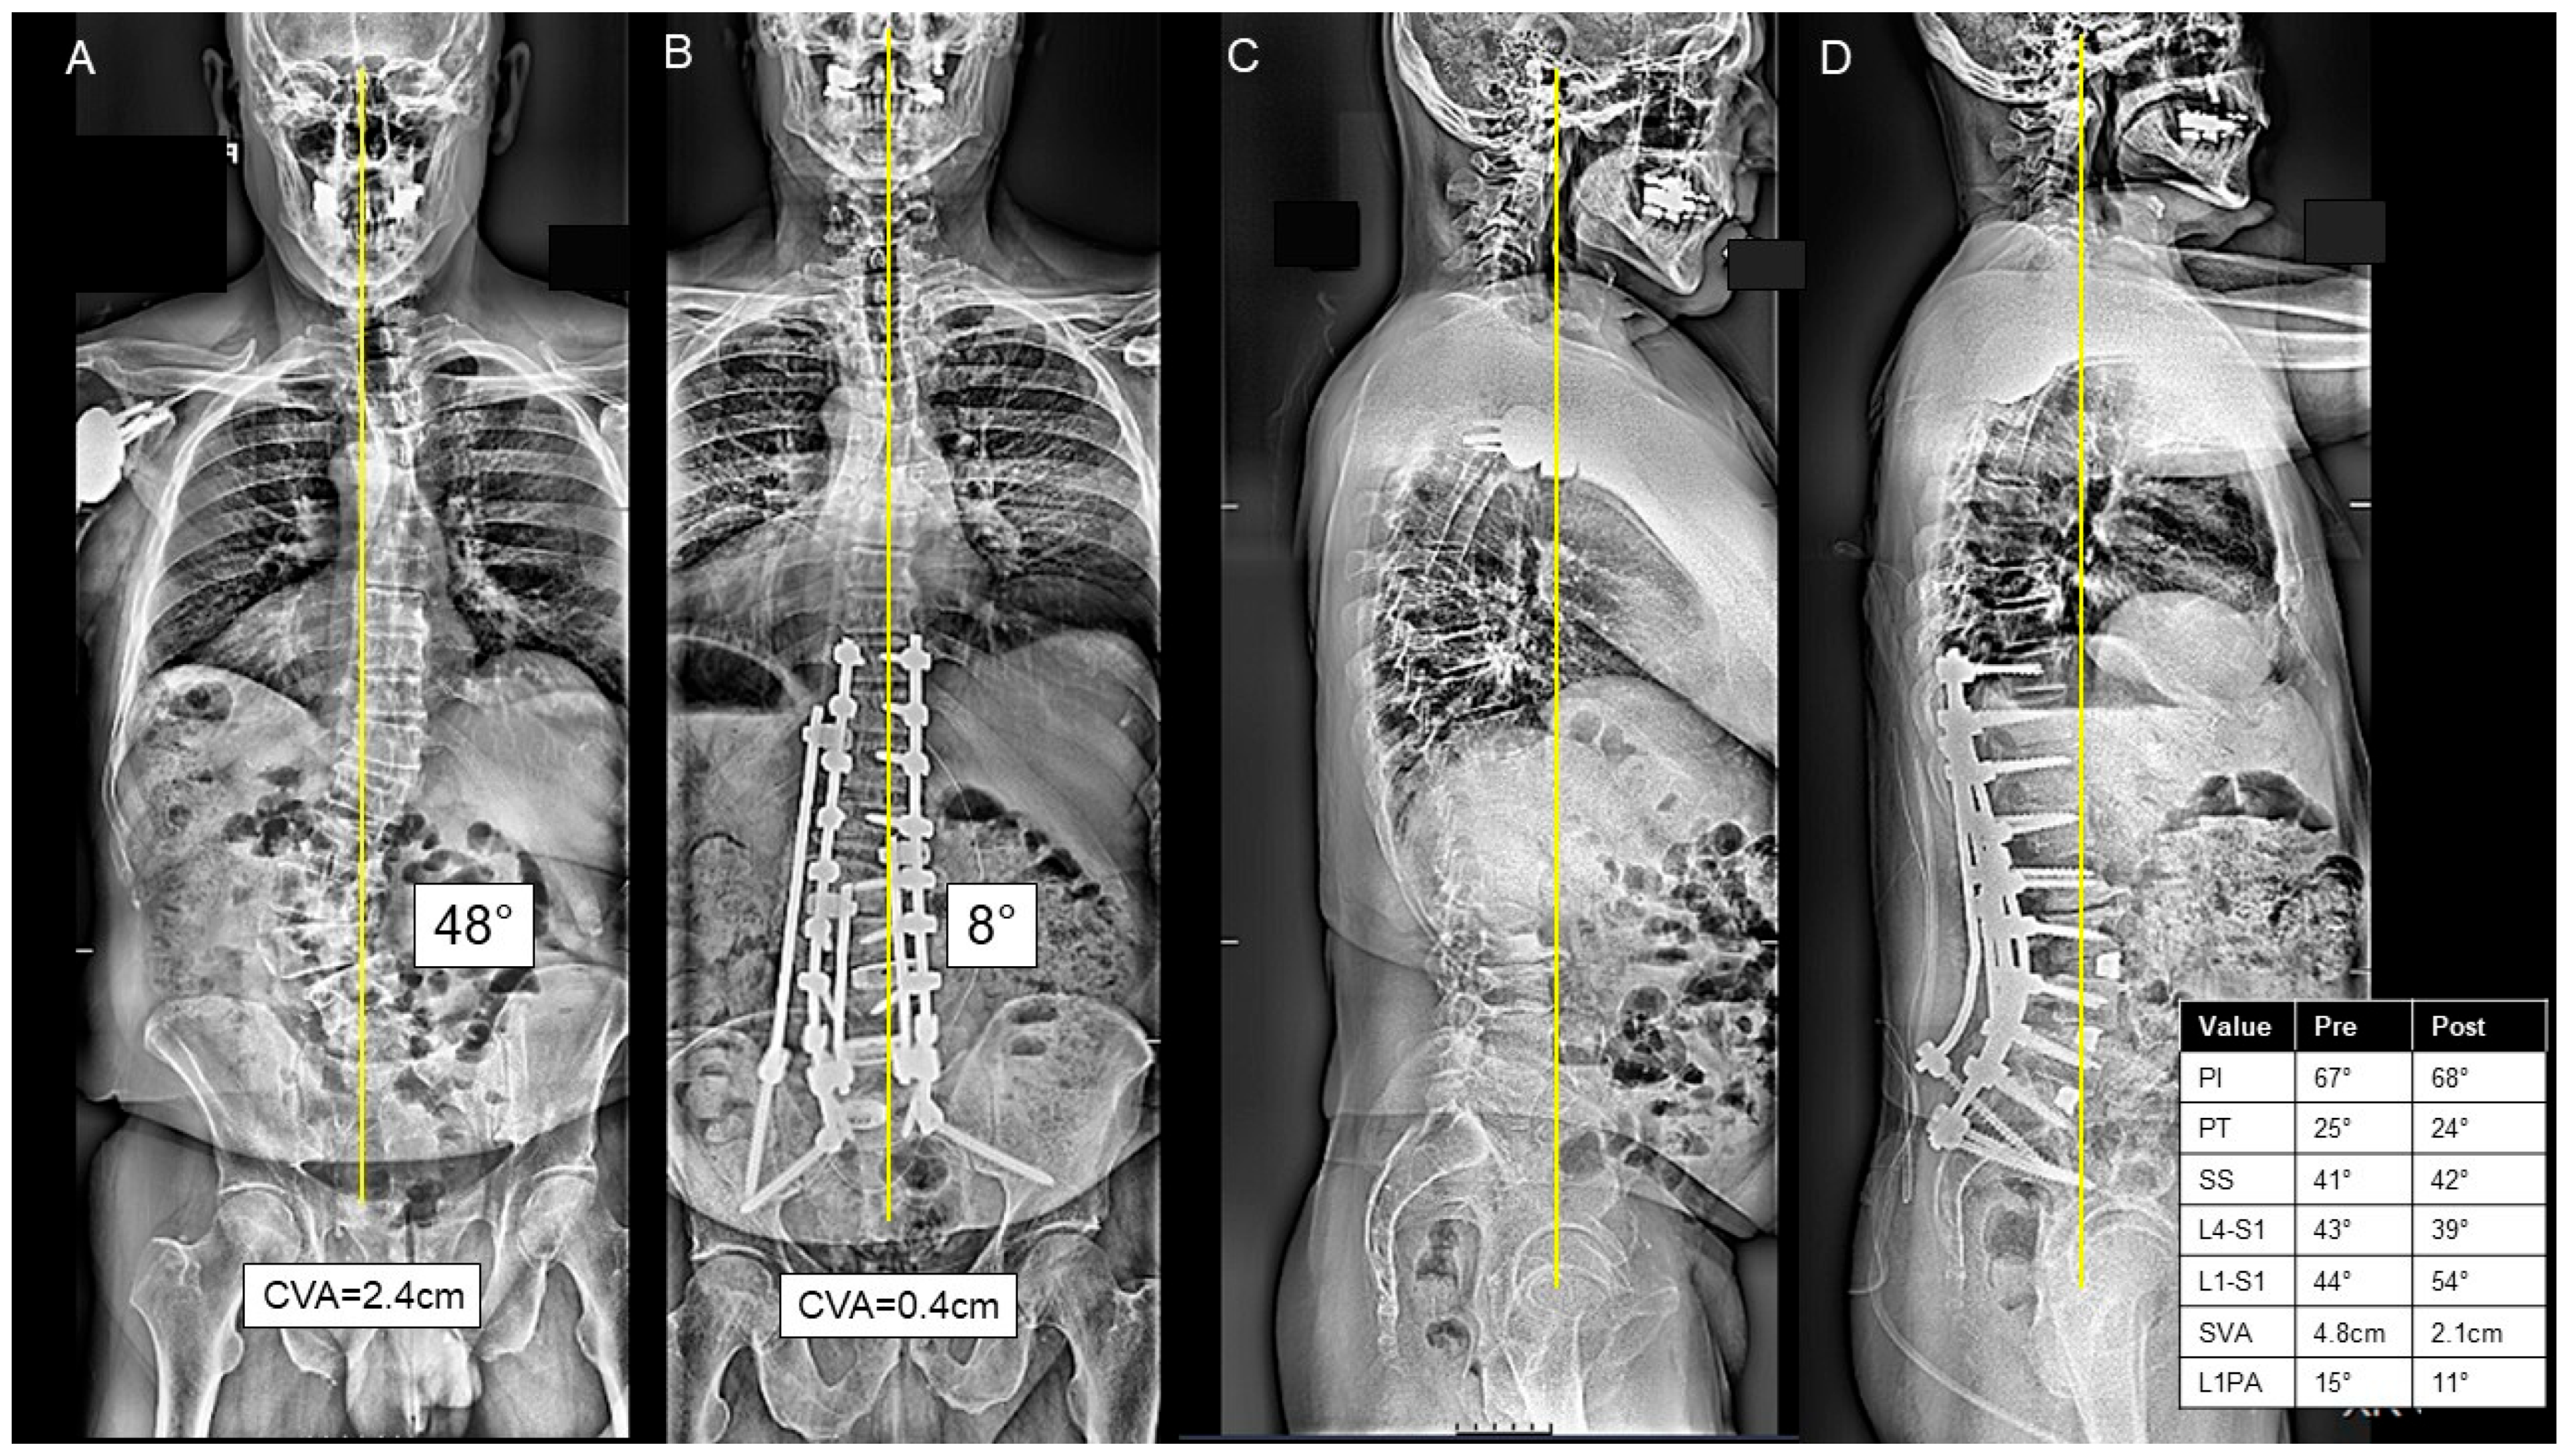

For patients in the AP group, the anterior approach consisted mostly of ALIF at L5/S1 (73.5%), L4/L5 (38.0%), L3/L4 (17.6%), L2/L3 (17.6%), and L1/L2 (2.9%). At L5/S1, the mean height of the implant was 10.9 ± 3.0 mm, and mean lordosis was −23.2 ± 32.5°. At L4/5, the mean height of the implant was 10.2 ± 3.0 mm, and mean lordosis was −10.7 ± 16.2°. Half of the AP cases were staged 18 (52.9%), separated by a mean of 2.1 (range 1–5) days. A three-column osteotomy was performed in 10 (29.4%) cases. A thoracolumbar UIV to sacrum/pelvis fusion was performed in 16 (47.0%) cases, and an upper/middle thoracic to sacrum/pelvis fusion was performed in 15 (44.1%) cases. A representative combined AP case is presented in Figure 3A–D.

Figure 3.

(A–D) A case presentation of a 67-year-old male presenting with L3-L4 left-sided radiculopathy and sagittal malalignment due to lumbar kyphosis causing severe mechanical back pain on the postero-anterior (PA) (A) and lateral X-rays (C). The patient underwent a stage 1 anterior lumbar interbody fusion at L4-5 and L5-S1. Two days later, the patient underwent a posterior approach consisting of T10-ilium instrumentation, posterior column osteotomies from T12-L5, inferior facetectomies from T10-S1, and L2/L3 and L3/L4 transforaminal lumbar interbody fusion, as seen on the postoperative PA (B) and lateral X-rays (D). The patient was discharged to IPR at postoperative day 9.